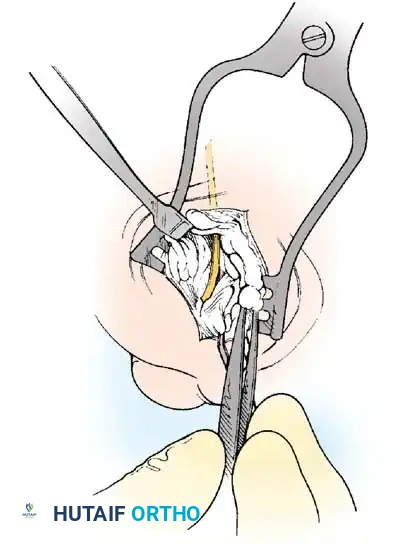

• Using a Freer elevator or a small osteotome for its strength, mobilize the fi bular sesamoid (Fig. 78-31A to C). This may be diffi cult in elderly patients with signifi cant deformity and adherence of the sesamoid to the metatarsal head. Lift the metatarsal dorsally for exposure (Fig. 78-31D and E).

Fig. 78-31 Excision of fi bular sesamoid in modifi ed Keller procedure. With base of proximal phalanx removed and medial eminence excision, exposure of fi bular sesamoid is not as diffi cult from medial incision. A, Operative photograph showing elevation of fi rst metatarsal with strong two-tooth retractor and use of small osteotome to mobilize fi bular sesamoid and lateral capsuloligamentous (frequently contracted) structures. Osteotome is between metatarsal head and lateral sesamoid. When mobilization of fi bular sesamoid is complete, entire sesamoid is visible for excision. Note chondromalacia of tibial sesamoid articular surface medial to osteotome. B, Fibular sesamoid has been excised, and lateral capsular structures and conjoined tendon (in forceps) have been released. Neurovascular bundle to lateral side of hallux is adjacent to these structures. C, Diagrammatic representation of modifi ed Keller procedure. By excising fi bular sesamoid, valgus moment of conjoined tendon of fl exor hallucis brevis and adductor hallucis no longer pulls fl exor hallucis longus tendon laterally (carrying hallux with it) through capsulosesamoid plantar plate and pulley system. D, Metatarsal head must be lifted dorsally to excise fi bular sesamoid under direct vision. E, Note exposure of fi bular sesamoid after mobilization of metatarsal head. Continued